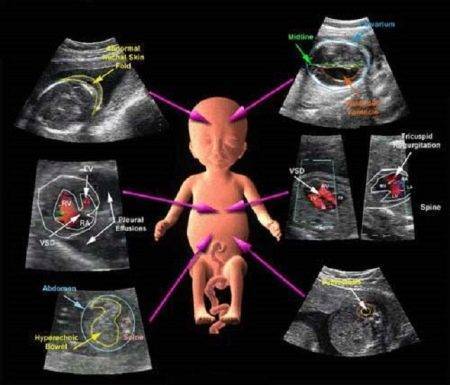

Информацию о пороках развития плода получают на 1-м УЗИ. Врач исследует размер воротниковой зоны. Значительные отклонения от нормы свидетельствует о разных заболеваниях, в том числе о синдроме Дауна.

Обязательно проверяется наличие печени, почек, сердца, позвоночника, мочевого пузыря, верхних и нижних конечностей. Если какой-то из органов отсутствует, то ставят вопрос о прерывании беременности. В любом случае все аномальные диагностируемые состояния повторно проверяются у генетика.

- Патологии плода на УЗИ лучше всего заметны именно на этом сроке. Для исключения вероятных проблем проверяется наличие формирующихся органов, ручек и ножек. Часто на этом сроке заметен даже пол ребенка. Отсутствие любой части тела свидетельствует о врожденных аномалиях.

Выявление сердечных пороков необходимо. Современные методики позволяют выявлять такие дефекты достаточно эффективно. Патологии развития сердечных клапанов и появление на них патологических потоков крови (регургитации) могут стать показанием для проведения хирургической коррекции сразу же после рождения ребенка.

С помощью УЗИ на этом сроке беременности можно выявить также и различные аномалии развития почек и мочевыводящих путей у плода. Квалифицированные специалисты могут также определить и формирующиеся патологии лоханки и мочевого пузыря. Наряду с исследованием мочевыводящей системы, доктор обязательно оценивает работу желудочно-кишечного тракта и дыхательной системы у плода.

Исследование позвоночника у малыша проводится только при подозрении на наличие генетических или хромосомных заболеваний. Для этого врач УЗИ исследует линейное сечение позвоночника. Изучаются также и остистые отростки. Если во время исследования специалист УЗИ выявил какие-либо существенные дефекты и у него возникли подозрения о наличии признаков хромосомных болезней, то он направит будущую мамочку на консультацию к генетику.

Анатомия плода. Соответствие показателей внутренних органов норме оценивается комплексно. Учитываются не только конкретные размеры, но и качество визуализации на УЗ-мониторе, общее состояние, взаимоотношения, соразмерность. Оцениваются:

- кости мозговой части черепа (отсутствуют при анэнцефалии);

- головной мозг в целом и состояние его ликвороносных путей (боковые желудочки, большая цистерна);

- лицевой череп (глазницы, носовая кость, носогубный треугольник). Уменьшение размеров носовой кости характерно для синдрома Дауна. Перерывы сигнала в зоне носогубного треугольника указывают на расщелины губы и нёба;

- как сформированы конечности;

- позвоночник: непрерывность, форма позвонков;

- легкие;

- сердце: количество сердечных камер, их соотношение.

- желудок, кишечник, печень;

- целостность брюшной стенки – для исключения грыжи пупочного канатика или расщелины;

- почки и мочевой пузырь – наличие, размеры, структура. Двухстороннее расширение лоханок – косвенный признак трисомии 21 пары;

- строение наружных половых органов помогает узнать пол ребенка.